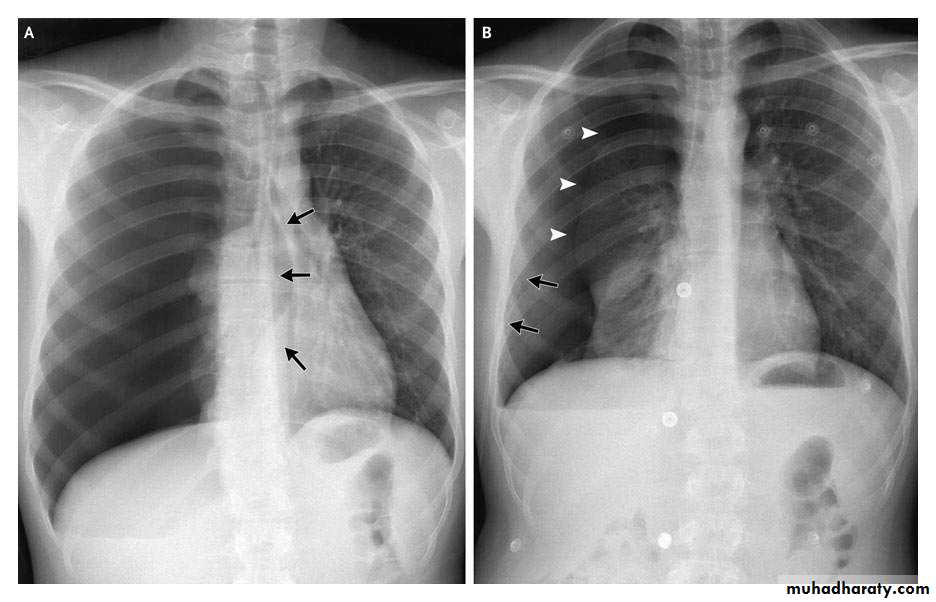

Pathogenesis

1. Acute or exudative phase

Thin pus, Thin pleura, Expandable lungs

2. Transitional or fibrinopurulent phase

Pus thicker, fibrin deposition, lung less expandable

3. Chronic or organization phase

Thick pus, thick pleura with fibrous coat, non expandable lungs (fibrothorax)